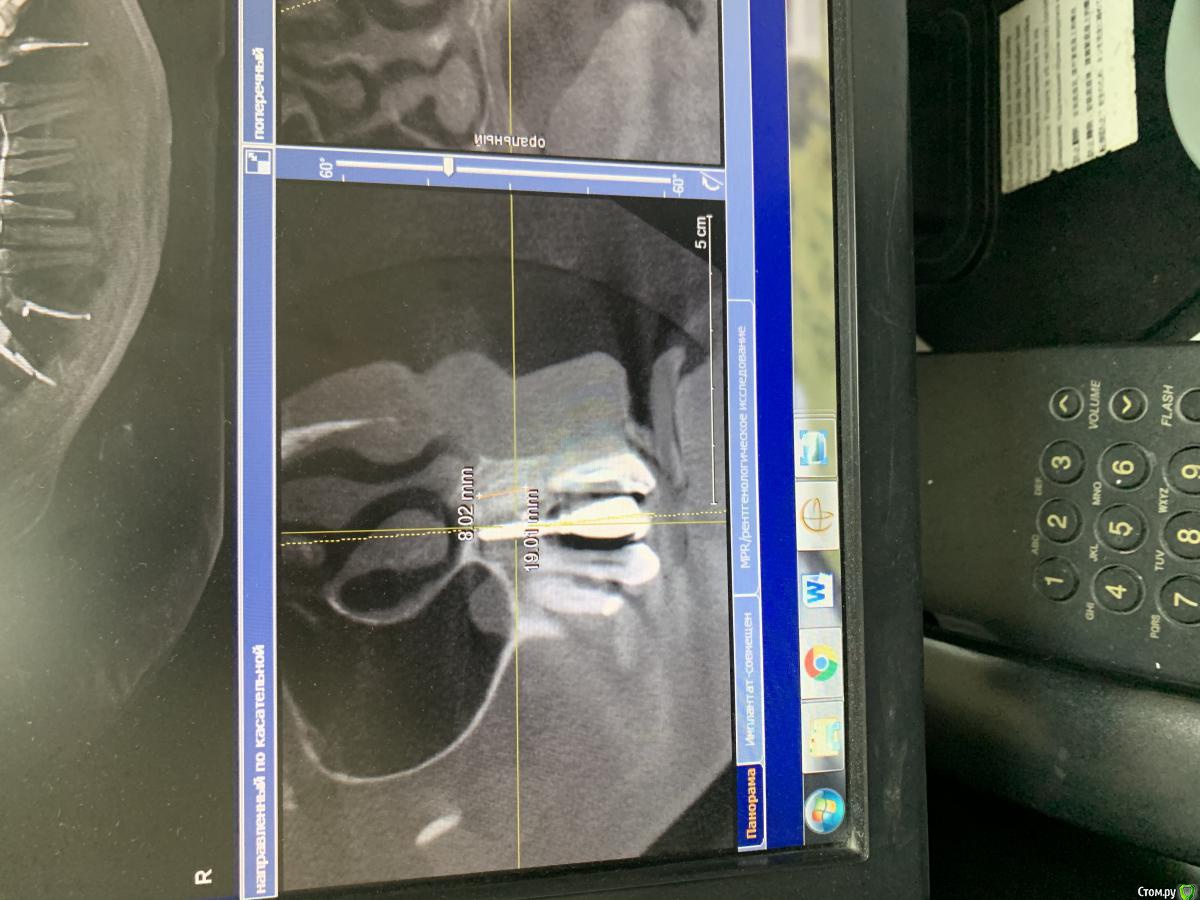

pavlin Опубликовано 12 ноября, 2019 Поделиться Опубликовано 12 ноября, 2019 (изменено) Планируется удаление 11 21 22 и имплантация в этой обл . Импланта в обл 12 ставили в др клинике несколько лет назад . Вопрос - тк кость в обл зубов ушла практически полностью , ставить Имплант как вОбл 12 (до носовой пазухи 8 мм ) тогда колонковая часть получается огромной ? Изменено 12 ноября, 2019 пользователем pavlin Ссылка на комментарий

pavlin Опубликовано 13 ноября, 2019 Автор Поделиться Опубликовано 13 ноября, 2019 ИМХО тут в руки щипцы и планировать с ортопедом высоту гребняА нормально будет , что Импланта высота 7-8 мм , а коронковая часть более 20 мм? Не вывернет ли имплант? Плюс по диаметру проходит только слим . Получается тонкий короткий Имплант и огромный рычаг в виде коронки Ссылка на комментарий